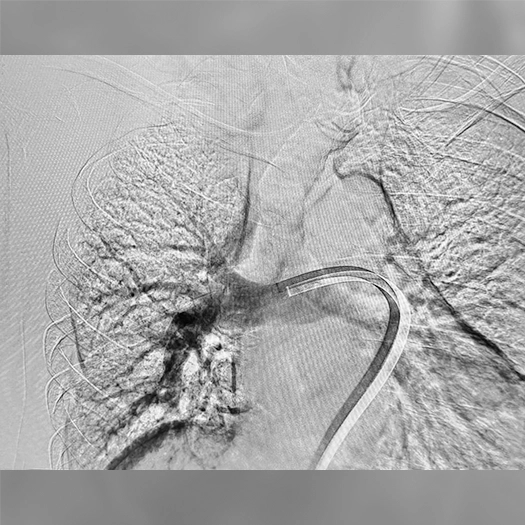

Attention was directed to the left main PA, which contained the majority of the thrombus burden. With the wire in place, the double-bend HTORQ tip configuration of the Lightning Flash 3.0 catheter facilitated seamless access into the left main PA for pre-thrombectomy imaging, revealing extensive thrombus. Aspiration was initiated, and the target thrombus was successfully removed in three passes.

Pre: Left pulmonary angiogram reveals extensive thrombus.

Post: Left pulmonary angiogram after aspiration.